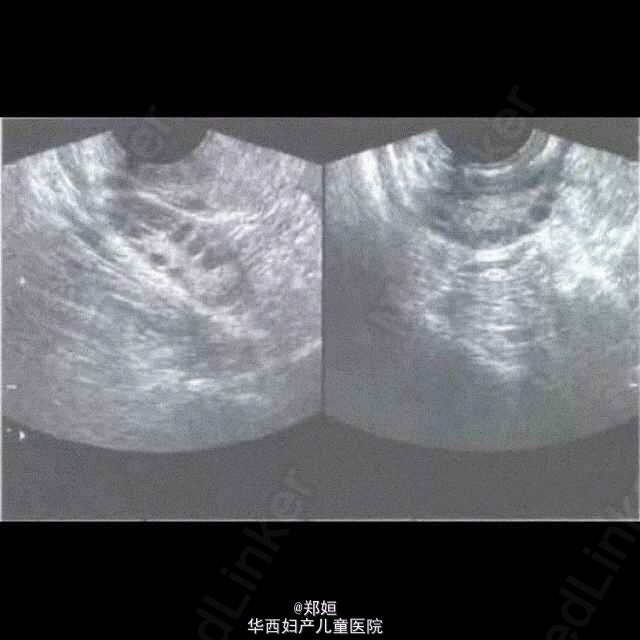

多囊卵巢综合征的超声诊断

PCOS是调节机制失常所产生的一种综合征,患者具有月经稀发或闭经、不孕、多毛和肥胖等一组症状,双侧卵巢呈多囊性增大改变。这有几个很好的超声诊断图跟大家分享一下吧。